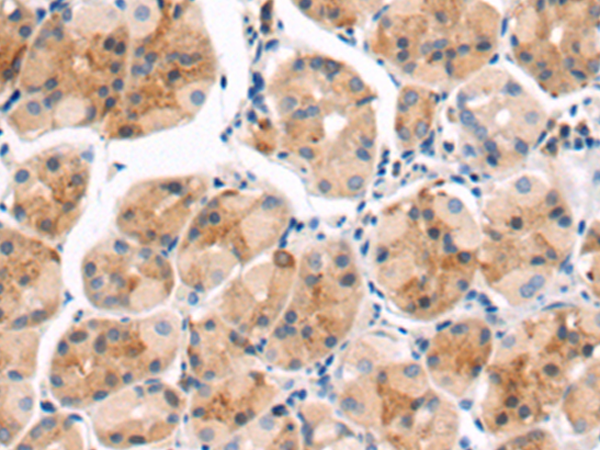

分类: 科研抗体货号: P07813别名: ALDH4; ALDH7应用: WB,IHC反应种属: Human, Mouse, Rat